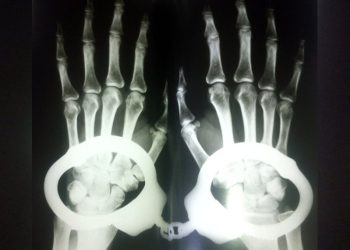

Read moreDetailsHasta tutuklunun kelepçeli bir şekilde muayene edilmesine dair verdiği şikayet dilekçesini cevaplayan Etlik Şehir Hastanesi yönetimi, kelepçeli tedavinin “tıbbi gerek...